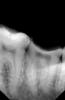

z1m14er Опубликовано 5 октября, 2013 Поделиться Опубликовано 5 октября, 2013 Пациентка, 26 летЖалобы: на выпадение пломбы из 37Анамнез: 37 ранее лечен несколько раз по неосложненому кариесу, последняя пломба ( в виде блина) простояла 6 лет.Объективно: Глубокая кариозная полоссть не сообщающаяся с полостью зуба. Дно полости практически на одном уровне со стенками, т.е. стенок как таковых нет. Дентин плотный, зондирование безболезненное, холодовая без последействия. Верхняя семерка Попова-Годона. Пространства для реставрации 37 нет (~2мм). Фото к сожалению нет, постарался подробно описать. Есть RVG. Посоветуйте пожалуйста, что можно предложить пациентке. Ссылка на комментарий

z1m14er Опубликовано 5 октября, 2013 Автор Поделиться Опубликовано 5 октября, 2013 Вы хотите сохранить пульпу? Все возможные варианты. Просто на снимке наверное не очень понятно, но зуб сохранен где-то 1-1.5 мм выше десны и до антагониста остается мм 2. Ссылка на комментарий